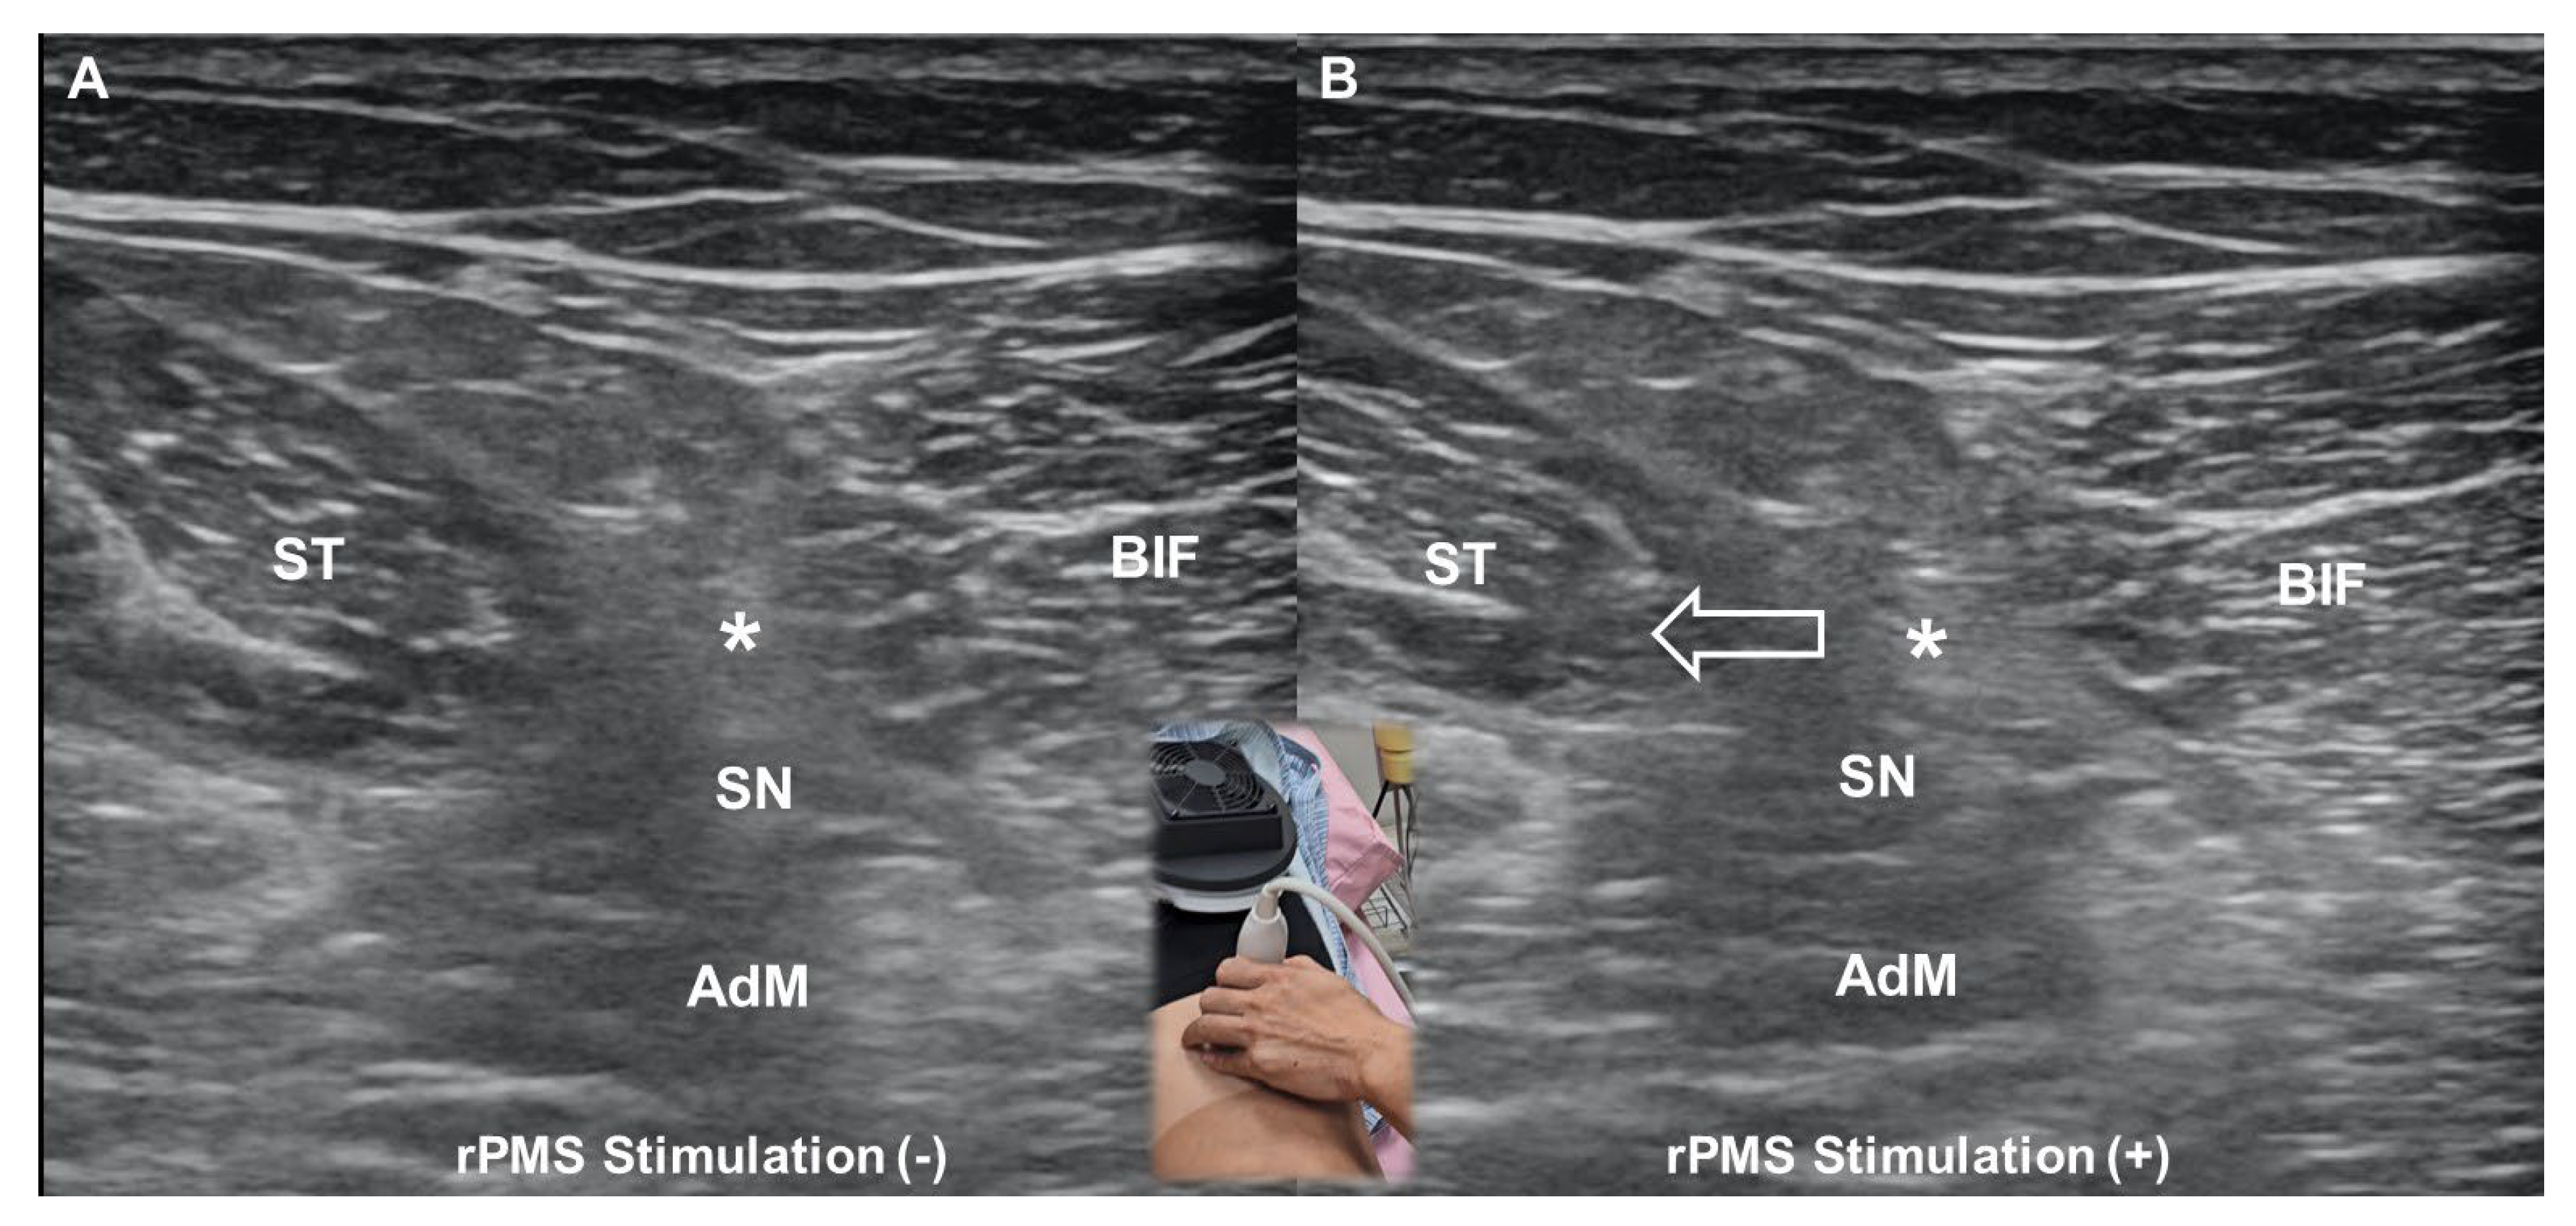

6. Repetitive Peripheral Magnetic Stimulation

6.1. Fundamental Principles

- Wu, W.T.; Chang, K.V.; Mezian, K.; Ricci, V.; Özçakar, L. “Sono-vision” of muscle contractions during peripheral magnetic stimulation. Med. Ultrason. 2025, 27, 106–107. [Google Scholar] [CrossRef] [PubMed]